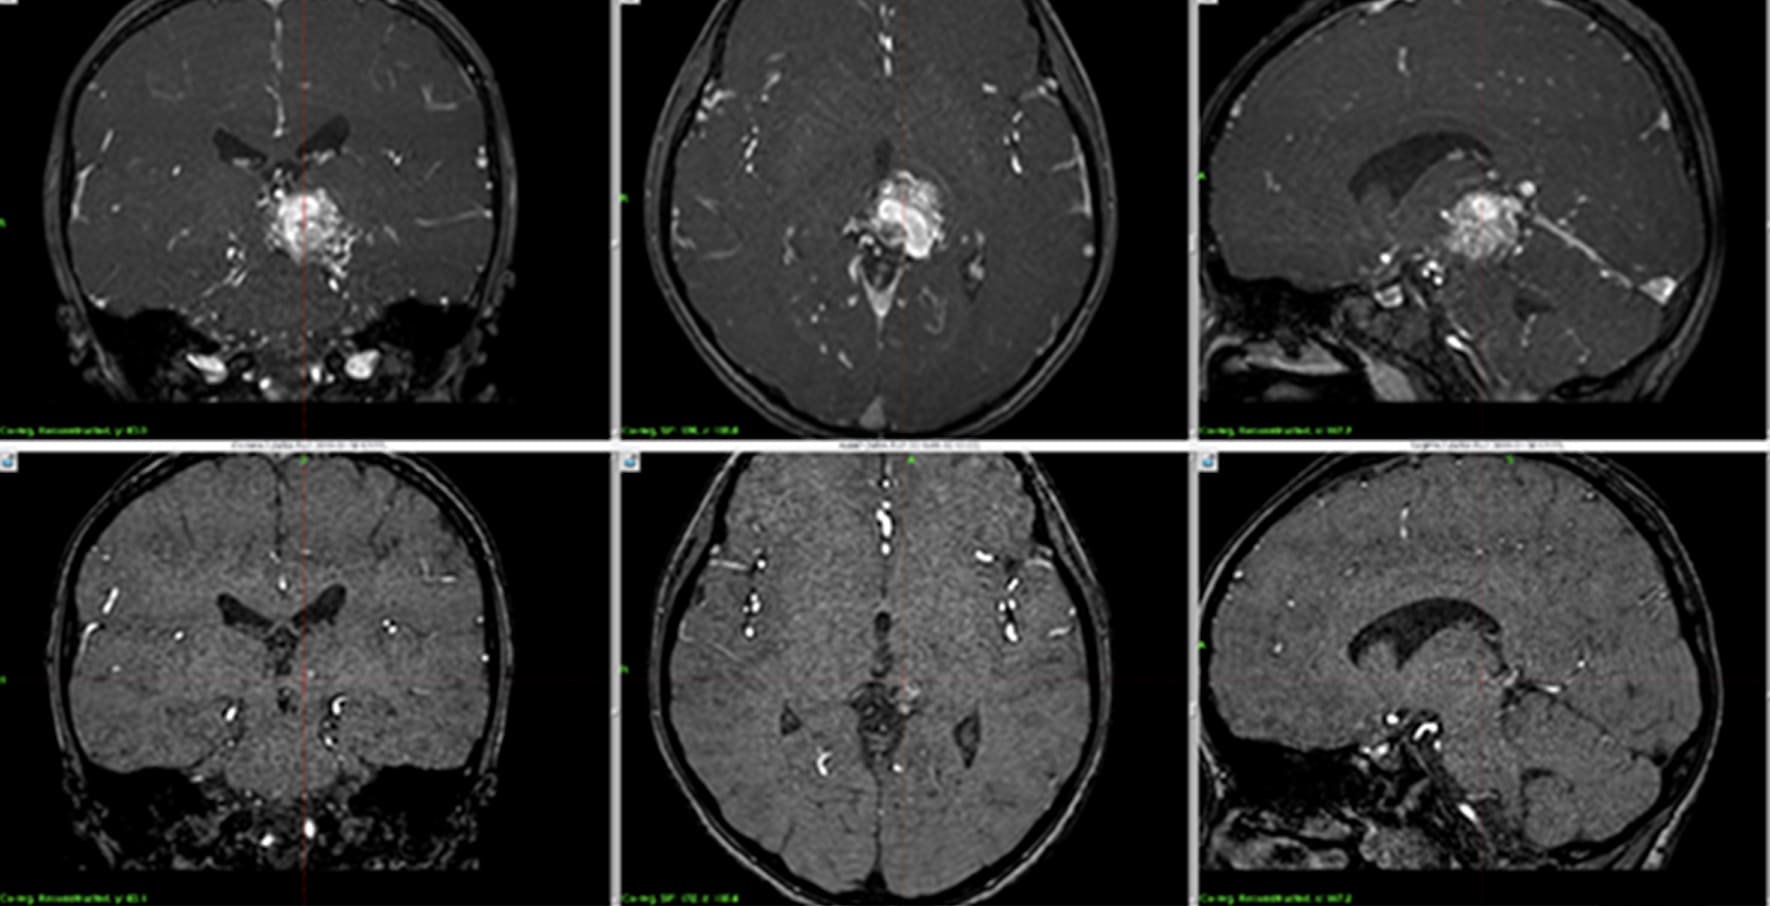

脳幹部高難易度AVM症例に対するガンマナイフ治療後経過

上段:治療前、下段:2年後にほぼ消失